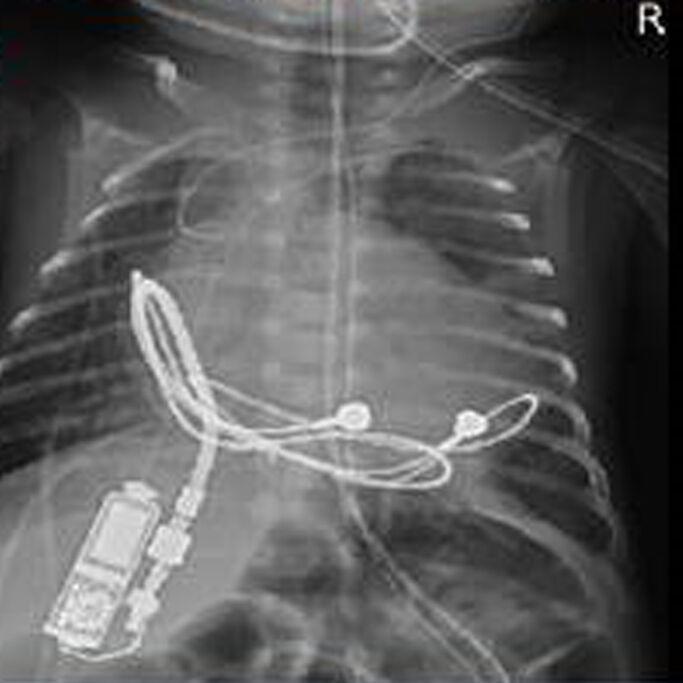

The open-heart surgery was completed in two hours, and the device measures 1.16 by 0.65 by 0.38 inches and weighs 0.18 ounces.

"While the operative steps might be comparative to the usual pacemaker implantation surgery, this surgery was especially delicate due to the very small size of the baby," Bahaaldin Alsoufi, M.D., chief of pediatric surgery and co-director of Norton Children's Heart Institute as well as a professor of cardiothoracic surgery at UofL, said in a statement. "This tiny pacemaker generator was positioned in the abdominal wall on the right side and was connected to the usual leads that were attached to the heart. This novel device will provide the necessary support that the baby currently needs. At time of repair of the patient's congenital heart defect in the future, we will be able to utilize these same leads and likely connect them to a traditional larger pacemaker generator."